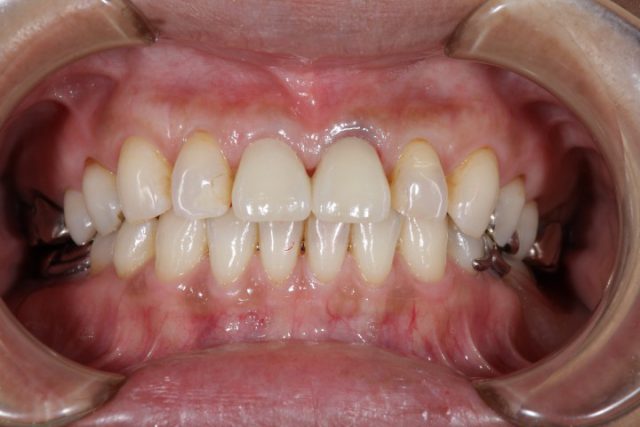

施術後

今回のように以前に施術した詰め物が変色したり、場合によっては欠損してしまったりの時に思い切ってオールセラミックによる施術を検討されてはいかがでしょうか。

歯のストレスというのは小さなことに思えますが、患者様のほとんどが施術後に大きなストレスだったと気づかれます。是非一度口の中にストレスがないかどうかセルフチェックしてみてくださいね!